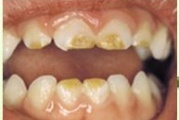

Tetratsükliini liigtarbimise tõttu värvunud hambad

Fluoroos

Fluoroosi

Hammaste defektid